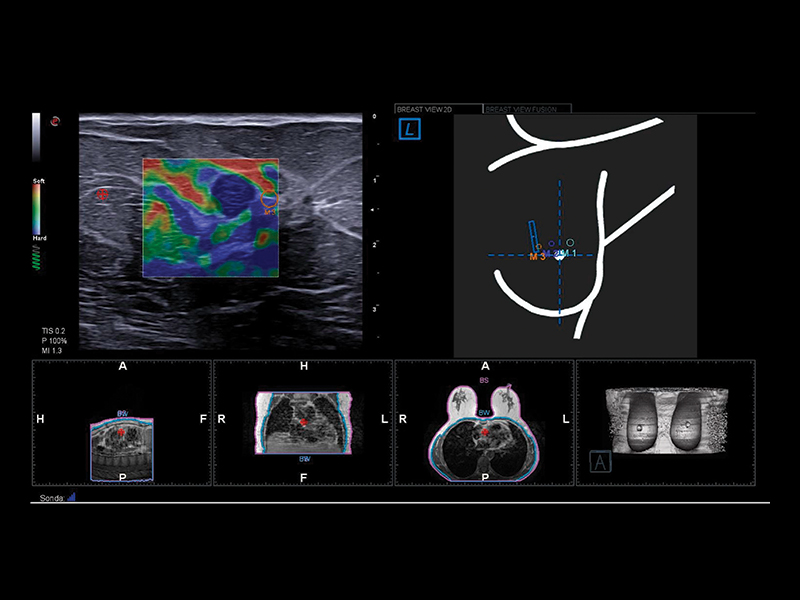

microV is Esaote’s new Doppler technology with an astonishing degree of sensitivity, even in very small vessels and slow flow detection; ElaXto, strain elastography, for real-time assessment of the relative stiffness of breast tissues; QElaXto 2D, 2D shearwave elastography, for mapping and quantification of tissue stiffness; and microE an algorithm for the enhancement of hyperechoic structures.

BreastNav™ & BreastNav™ MRI offer the full breast package for a multimodality approach in one of the most mobile and variable organs in the human body, giving real-time feedback on the scanned area for easy follow-up on a specific target.

BreastNav™ MRI is a unique feature in the market, which can perform real-time fusion imaging on the breast between the prone MRI and supine US datasets, based on 3D-model adaptive A.I. technology, aimed at supporting second-look examinations.